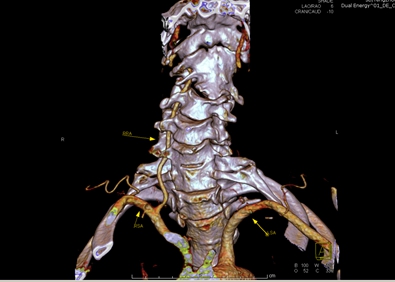

圖1示患者術前頸椎椎體部分融合、側彎畸形